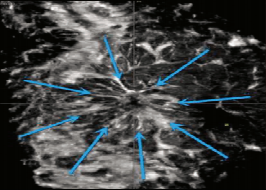

(2)跳跃征(skipsign):扫描过程中出现的部分删除伪像或跳跃伪像,见图9。由于探头通过乳腺不同硬度的区域或轮廓变化而发生,在可触及(质地较硬)、表面或较大的肿块及致密型乳腺中常见,对于肿块病灶的良恶性鉴别意义不明,但有研究报道是非肿块恶性病变的预测因子[6]

什么是超声容积探头【解读】自动乳腺容积超声技术专家共识 (2022 版)_https://www.jmylbn.com_新闻资讯_第14张

图9 跳跃征

较大的低回声肿块边缘出现跳跃伪像。